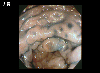

A case of MLP (multiple Lymphomatous Polyposis) type malignant lymphoma which involved the G1 tract including the esophagus.

Endoscopy

Malignant Lymphoma/MLP type